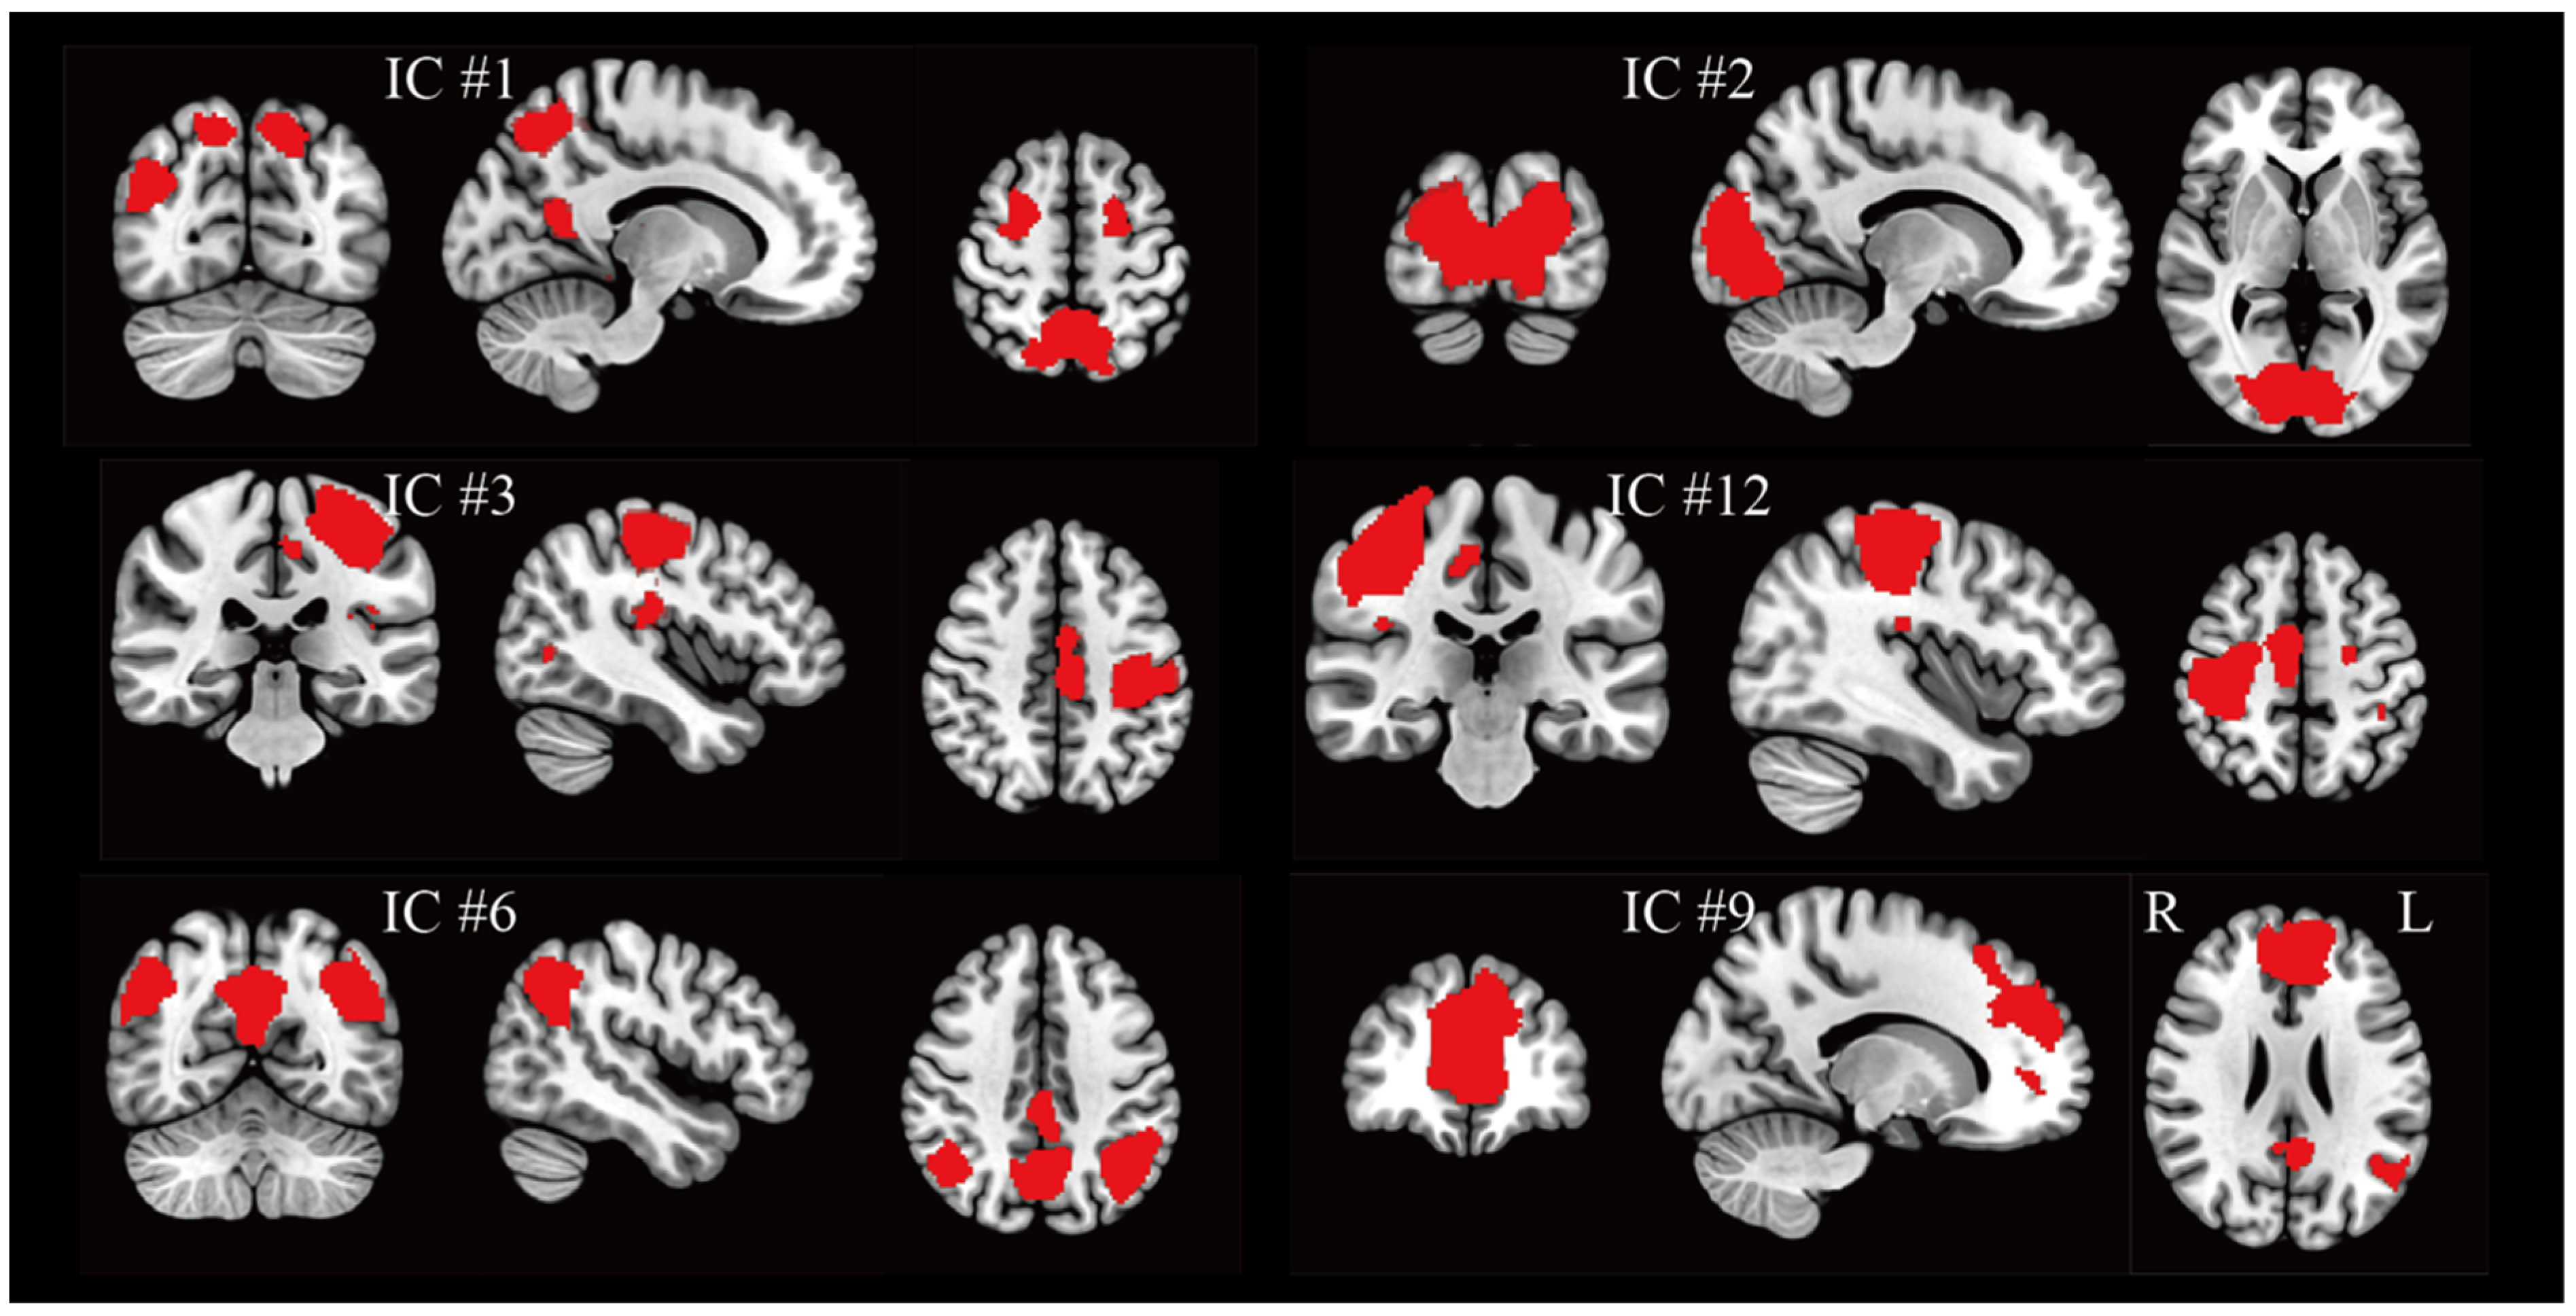

3.1. Group Networks Under BCI Regulation